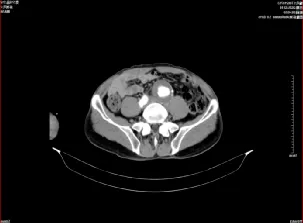

据悉,61岁的李爹爹来院就诊,经检查确诊为腹主动脉夹层合并髂动脉瘤,并伴有瘤壁血栓,病情危重,随时可能危及生命。面对如此复杂的病例,医院高度重视,立即组织心血管病科、普外科、麻醉科、医学影像科等多学科专家进行会诊。专家团队仔细分析患者病情,充分评估手术风险,最终制定了详尽的手术方案和应急预案。

在上级教授的指导下,夏贤龙副主任介入团队凭借精湛的技术和默契的配合,成功为患者实施了腹主动脉髂动脉覆膜支架植入及右侧髂内动脉瘤栓塞术。手术过程顺利,患者术后恢复良好,目前已康复出院。